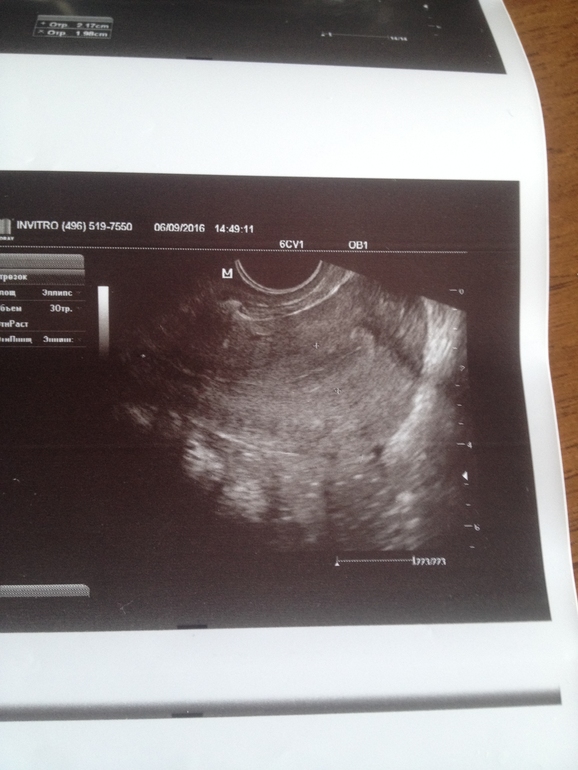

на 3 фото матка.